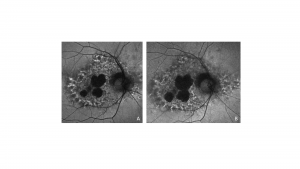

Characteristic features of PPS maculopathy were defined in one study as the following: “(1) bilateral pathology centered on the fovea; (2) fundus photography revealing paracentral macular hyperpigmented spots, pale yellow deposits, and/or patchy retinal pigment epithelium atrophy; (3) a dense array of hyper- and hypoautofluorescent spots and reticular fundus autofluorescence imaging abnormalities; and (4) foci of nodular retinal pigment epithelium enlargement on OCT imaging corresponding to hyperreflectance on near infrared reflectance imaging.”[8]

Fundus photography, fundus autofluorescence imaging (FAF), optical coherence tomography (OCT), and near-infrared reflectance imaging (NIR) are useful imaging modalities to establish a diagnosis of PPS maculopathy. Imaging findings are typically symmetric between both eyes, with rare cases of disease asymmetry.[11][12][21]

Color fundus photography typically shows more subtle manifestations compared to FAF. Hyperpigmented macular spots and deep yellowish subretinal deposits may be apparent, particularly in milder cases.[11][12][15][16] Patchy parafoveal RPE atrophy manifests in more advanced cases.[7][11][12][31]

Fundus autofluorescence imaging reveals a striking, densely packed array of hyper- and hypoautofluorescent spots typically centered on and involving the fovea.[4][7][11][12] Hyperautofluorescent spots colocalize with pigmented spots and yellow subretinal deposits apparent on color fundus photography.[7][11][12] In cases where the disease extends to the periapillary region, there is typically a hypoautofluorescent peripapillary halo.[11][12] RPE atrophy may also be noted in more severe cases, initially as multifocal parafoveal lesions, that ultimately coalesce and encroach on the foveal center. Widefield FAF imaging is helpful to elucidate the extent of involved tissue.[11]

Optical coherence tomography shows hyperreflective nodules at the level of the RPE that colocalize with macular pigment clumps on color fundus photography, hyperautofluorescence on FAF, and hyperreflectance on NIR imaging.[7][11][12] Unlike typical drusen or subretinal drusenoid deposits, these lesions appear to reside at the level of the RPE and project a shadow onto the underlying choroid.[11][33] These lesions may not be present on macular OCT in late-stage atrophic disease.[11] Although there may be ill-defined irregularity in the outer retinal bands, there is no clear OCT correlate for yellow macular deposits or the hypoautofluorescent component of FAF lesions.[11][12] OCT angiography may be demonstrate choriocapillaris flow deficits, which may precede other imaging abnormalities in individuals with high PPS exposure.[13][14]

Near infrared reflectance imaging is another important imaging modality with prominent findings that may be present even in the absence of visible lesions in other imaging modalities.[12] Nodular hyperreflective lesions are visible on NIR that correspond to the pigmented lesions on color fundus photography and hyperreflective RPE excrescences on OCT.[7][11][12] Centrifugal progression of parafoveal hyperreflective lesions are noted which develop into hyporeflective areas due to EZ attenuation and RPE atrophy over time on NIR. [34]

Retinal pigment epithelium atrophy appears to be a manifestation of advanced PPS maculopathy.[11][12] It typically first develops as parafoveal multifocal atrophy that may coalesce over time and involve the foveal center.[11]